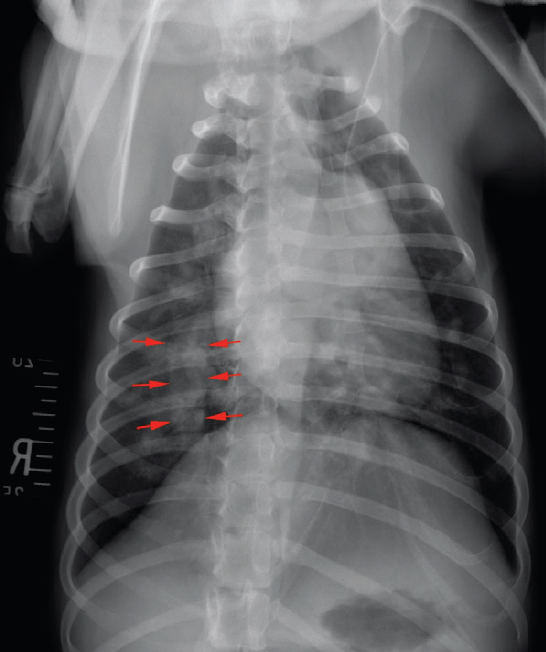

Thoracic radiographs revealed enlargement of the pulmonary arteries, mild to moderate right ventricular enlargement and a moderate diffuse, unstructured interstitial pattern with patchy alveolar areas within the right cranial and middle lung lobes (see Figures 1 and 2). Echocardiography revealed right atrial enlargement with bulging of the interatrial septum to the left, mild subjective enlargement of the right ventricle and mild to moderate central pulmonic regurgitation with a mildly elevated velocity (2.8m/s; reference value <2.2m/s). The pulmonary artery was mildly enlarged and contained multiple mobile, tortuous linear hyperechoic structures, likely to reflect the presence of adult worms (see Figure 3). The laboratory test results in combination with the imaging findings were consistent with a diagnosis of canine dirofilariasis.